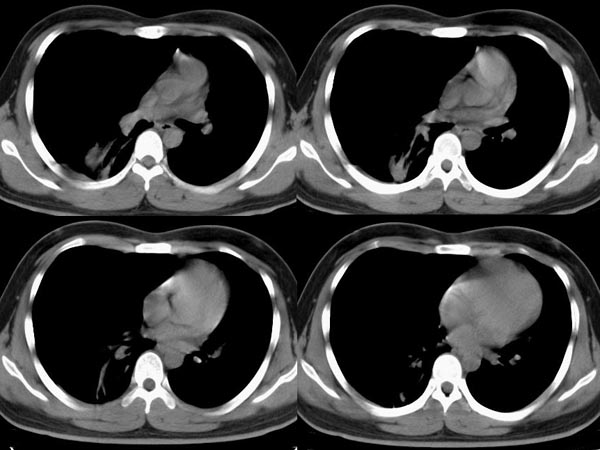

m21y既往体健,否认结核、支扩等病史;1周前患上感,无明显咳嗽,自觉无明显不适。单位体检透视时发现右侧液气胸!cr及ct如下(肺组织窗:l:-598hu w:1132hu):请大家会诊!!

右侧巨大含气囊性病变,壁薄、光整、其外侧见气体。右肺压迫性肺不张、胸腔内见少量积液。纵隔向左侧移位。左肺未见异常。诊断:1.右侧含气肺囊肿(先天性)。2.右侧液气胸。(少量液体)3.右肺压迫性肺不张。我也遇见一例这样的病人。女性。股骨外伤就诊。常规胸片发现右侧囊性病变。

1)考虑右肺巨大肺囊肿;肺大泡待排。2)右侧液气胸。3)右肺压迫性肺不张 。